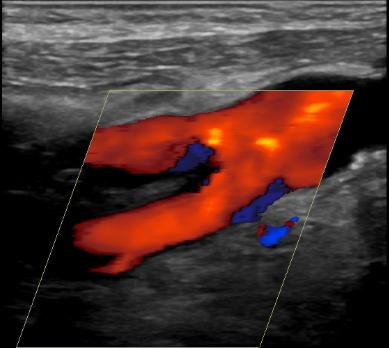

Duplex ultrasonography for imaging carotid arteries

Duplex ultrasound is a non invasive, safe and cheap method for imaging of blood vessels. The sensitivity of carotid duplex ultrasonography for detecting stenosis in the internal carotid artery is over 90{8ceaa46882e4d49283ff23b35262537230ad541262f55a031ead545e66522058} and so is the specificity. These figures become even more accurate in more severe disease (stenosis of over 70{8ceaa46882e4d49283ff23b35262537230ad541262f55a031ead545e66522058} versus 50{8ceaa46882e4d49283ff23b35262537230ad541262f55a031ead545e66522058}). Of note: duplex ultrasound is less accurate for diagnosing common carotid artery stenosis, but this disease is much less common and is therefore a less common cause of neurological symptoms.

Carotid duplex ultrasonography utilizes several measurement to estimate the degree of carotid stenosis:

- Internal carotid artery peak systolic velocity (ICA PSV) – Peak systolic velocity increases as stenosis increases, if it is hemodynamically significant.

- Plaque estimate

- The internal carotid / common carotid peak systolic velocity ratio

- Internal carotid artery end diastolic velocity (ICA EDV)